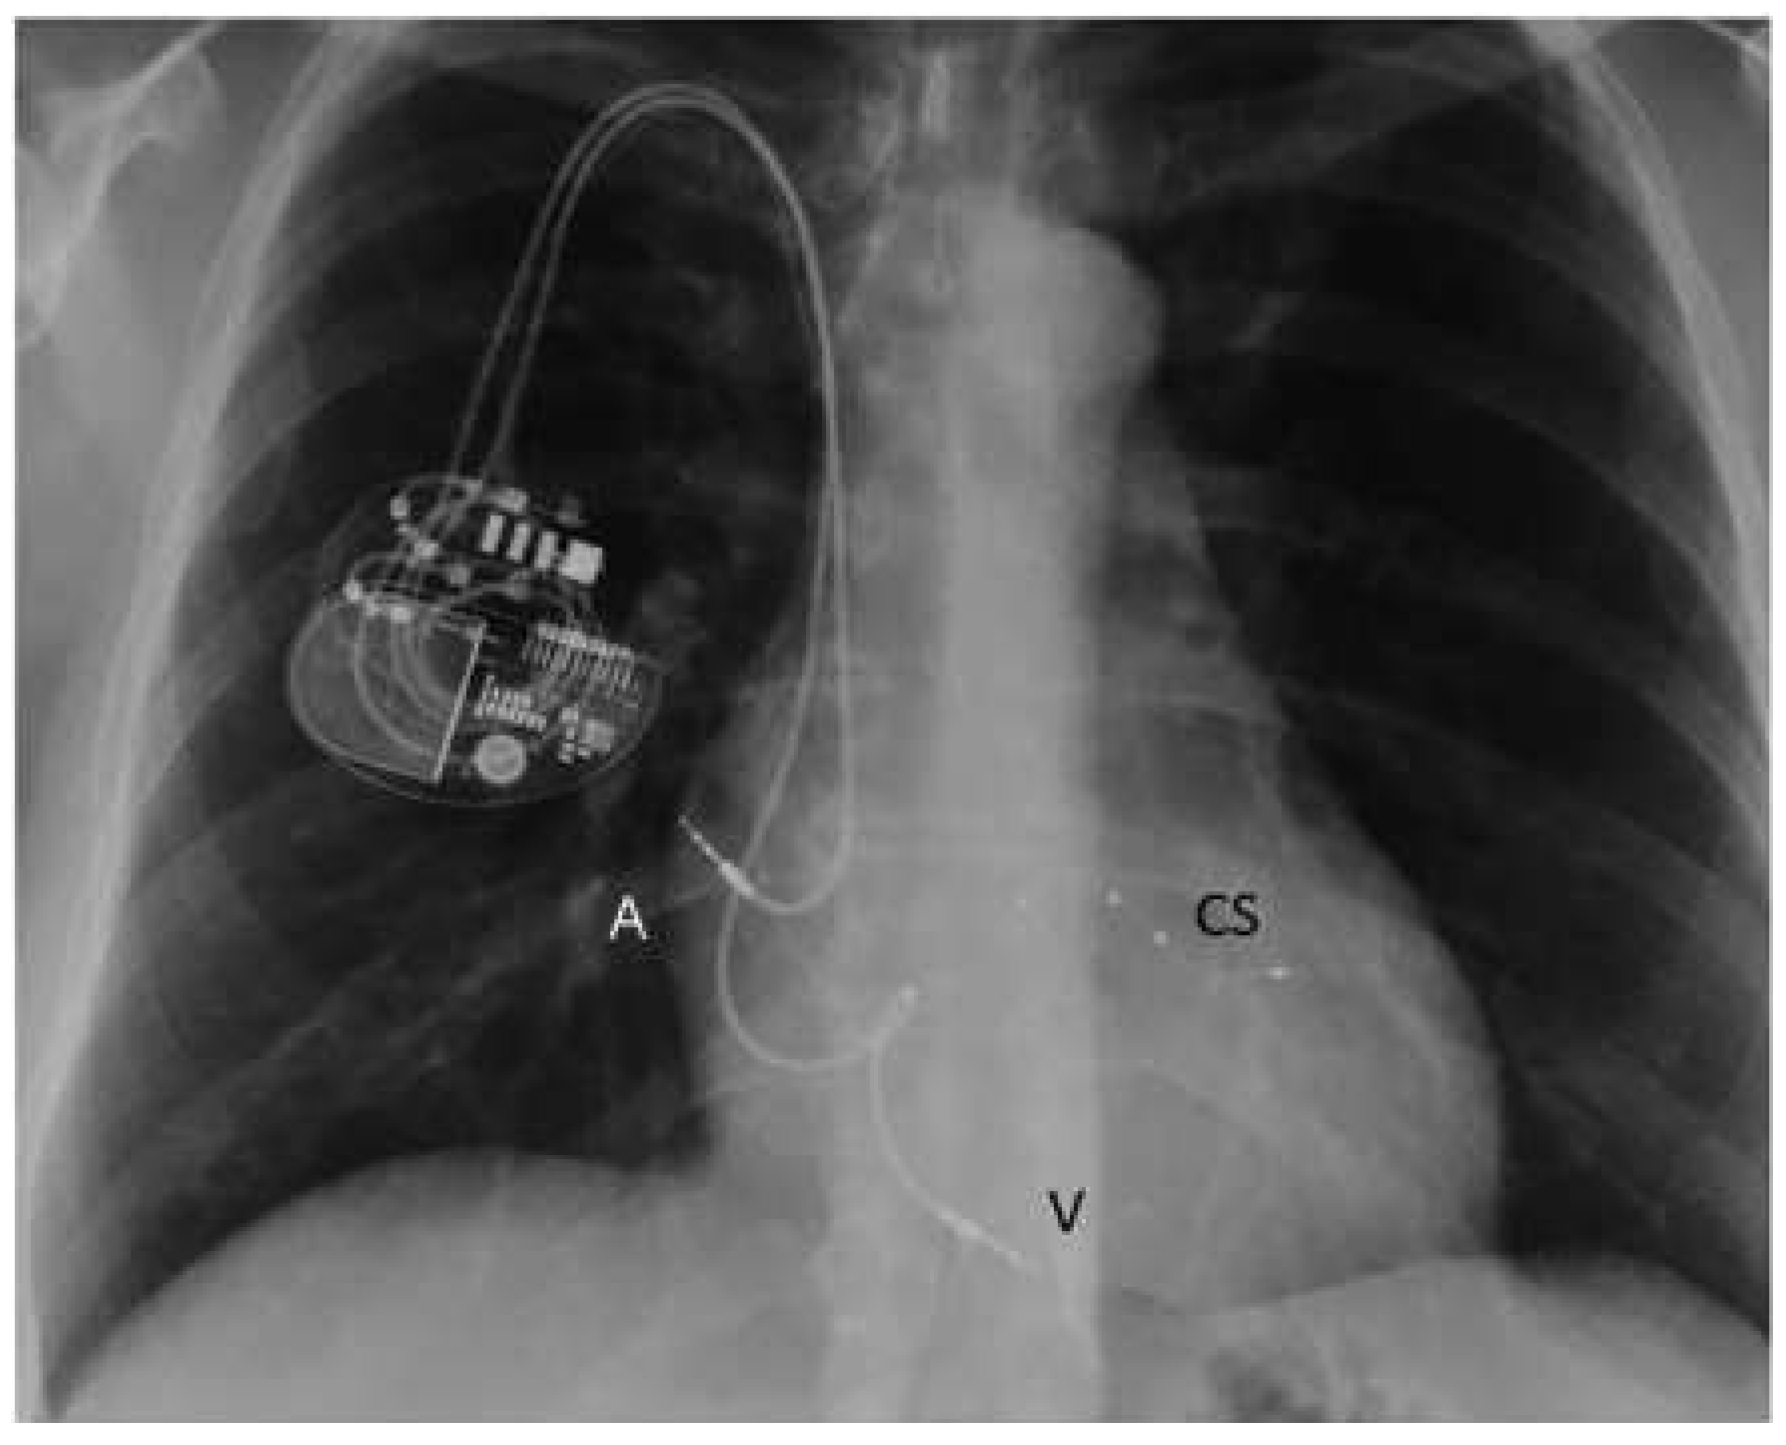

| CRT | cardiac resynchronisation therapy |